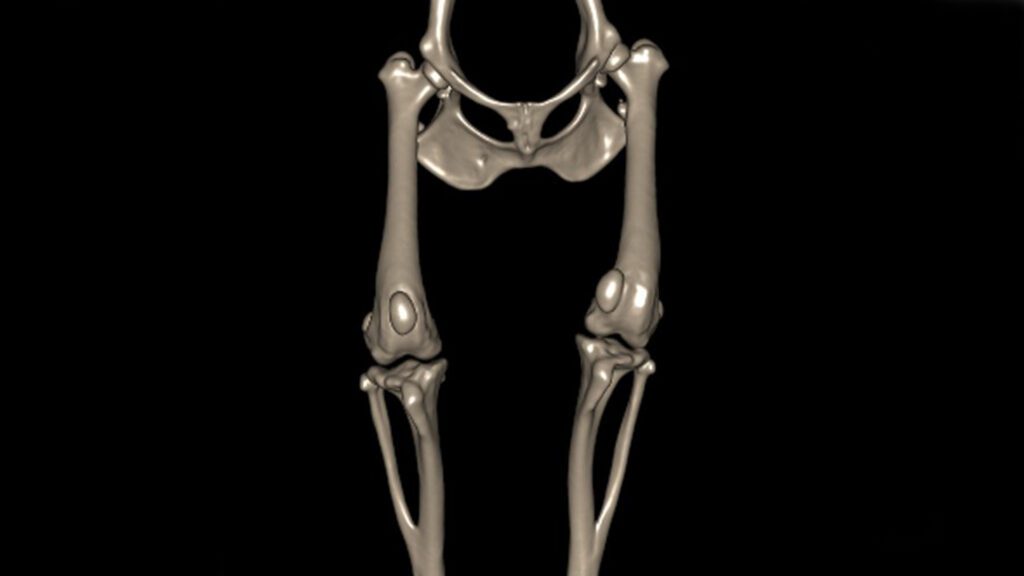

Growth deformities

We provide the greatest range of options for treating limb deformity, including techniques unavailable anywhere else in the world.